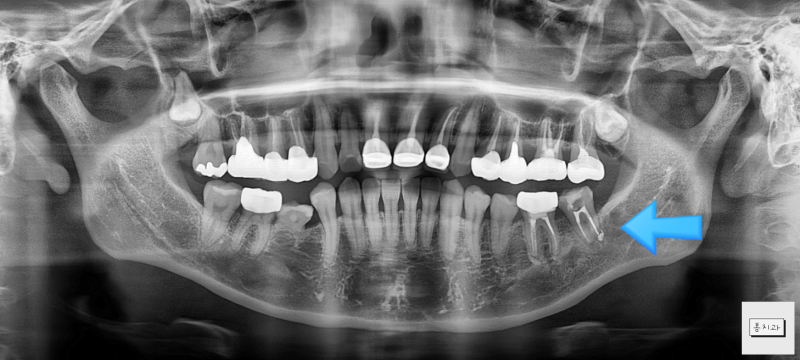

3d-ct 상에서도 걱정근관의 염증병소가 확인됩니다.이렇게 신경치료/재신경치료 후에도 병소가 재발할 수 있습니다.기존 치료와는 관계없이 치아 신경의 해부학적 구조와 관련이 있습니다.

치근 끝이 보이지 않는 미세구조(미세연결/부근관 등)는 신경치료 성공률을 떨어뜨리는 요인이 됩니다. 치근단 절제술을 통해 이러한 염증의 원인이 되는 치아 구조를 절제하고 mta로 밀폐합니다.